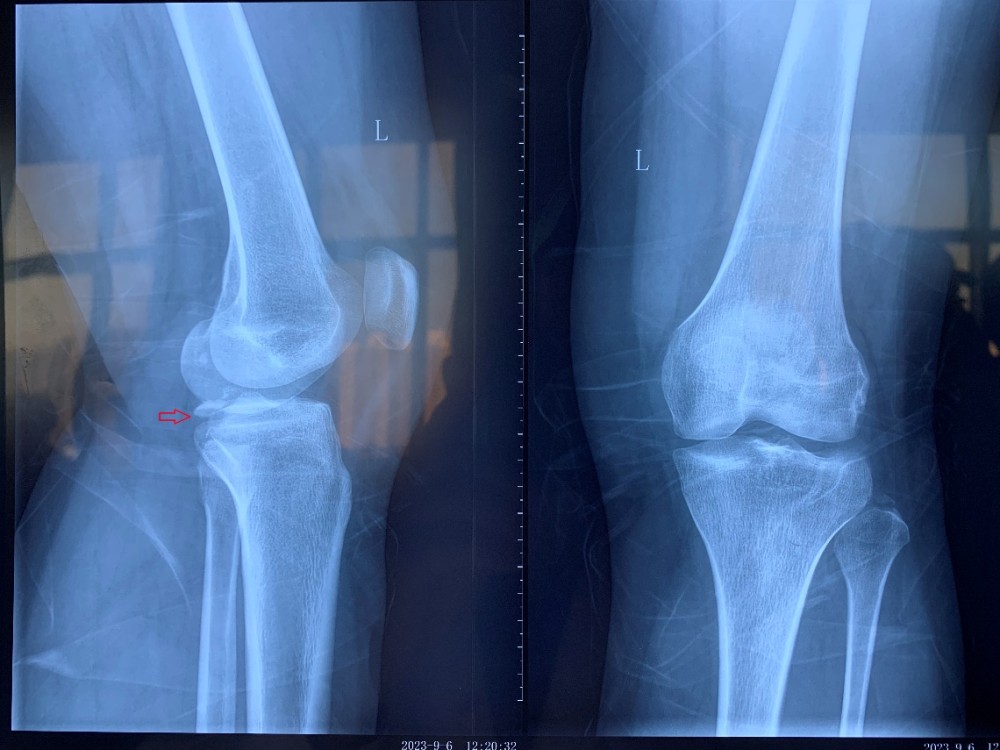

患者因外伤导致左胫骨髁间棘骨折,骨折移位明显,具备手术指征。但患者为年轻女性,担心手术瘢痕影响美观,传统手术方式无法满足患者需求。综合考虑后,91直播 创伤外科中心王建忠教授团队为患者制定了应用骨科手术机器人辅助下进行微创手术的诊疗方案。通过机器人进行数据采集、手术规划等人工智能手段,术中仅用约2cm切口即成功完成手术。与传统手术相比,此类手术切口明显减小,出血量少,达到了微创、精准的手术效果,患者及家属非常满意。

术前X线片